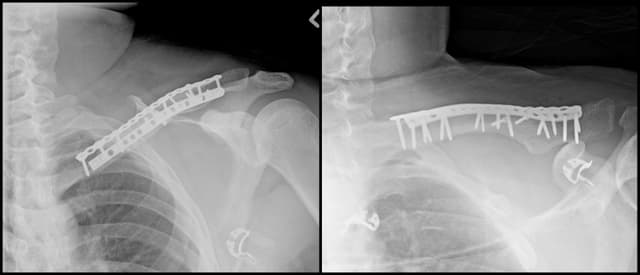

Pre-op

Post-op